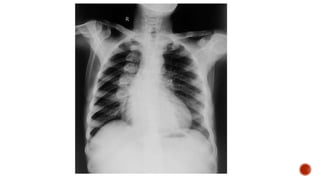

Frontal chest radiograph shows few ill defined patchy opacities in both the lung

fields, few of them showing cavitatory changes. TCC seen in situ.

Compared to the previous radiograph there is reduction in the number of opacities

with cavitatory changes.